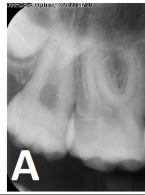

SPECJALISTA RADZI: Nieskuteczna apikotomia wierzchołka korzenia – ponowna resekcja czy powtórne leczenie kanałowe?

Zgłosiła się do mnie 60-letnia pacjentka z nieszczelną i nieestetyczną koroną protetyczną osadzoną na zębie siecznym szczęki. Pacjentka poinformowała, iż ząb był poddany przed laty zabiegowi resekcji. Wykonane zdjęcie potwierdziło wcześniej wykonaną apikotomię oraz obecność niewielkich zmian zapalnych w tkankach okołowierzchołkowych. W kanale stwierdzono dobrze kontrastujący się ćwiek (prawdopodobnie srebrny); w części koronowej kanału był widoczny krótki indywidualny wkład koronowo korzeniowy. Co mogę zasugerować pacjentce? Jakie są możliwości leczenia?